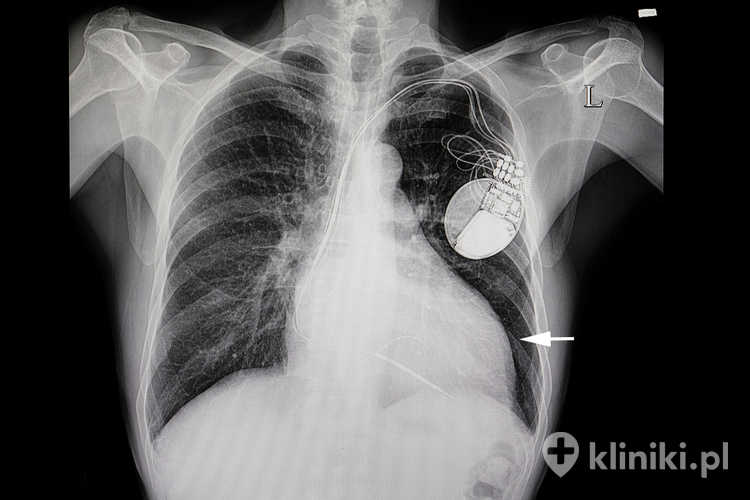

Pomimo wielu zalet badania za pomocą rezonansu magnetycznego, należy pamiętać, że bezwzględnym przeciwwskazaniem do przeprowadzenia tego typu diagnostyki jest obecność w ciele pacjenta wszczepionych urządzeń elektronicznych, takich jak rozrusznik serca czy aparat słuchowy.

Należy wziąć pod uwagę, że metalowe implanty i urządzenia medyczne, takie jak rozruszniki serca i defibrylatory, mogą ulec zakłóceniom lub uszkodzeniom pod wpływem silnego pola magnetycznego. Kochlearne implanty słuchowe również mogą stanowić przeciwwskazanie ze względu na możliwość ich uszkodzenia. Metalowe stenty, klipsy i protezy mogą reagować z polem magnetycznym, co prowadzi do ich przemieszczenia lub nagrzewania się.